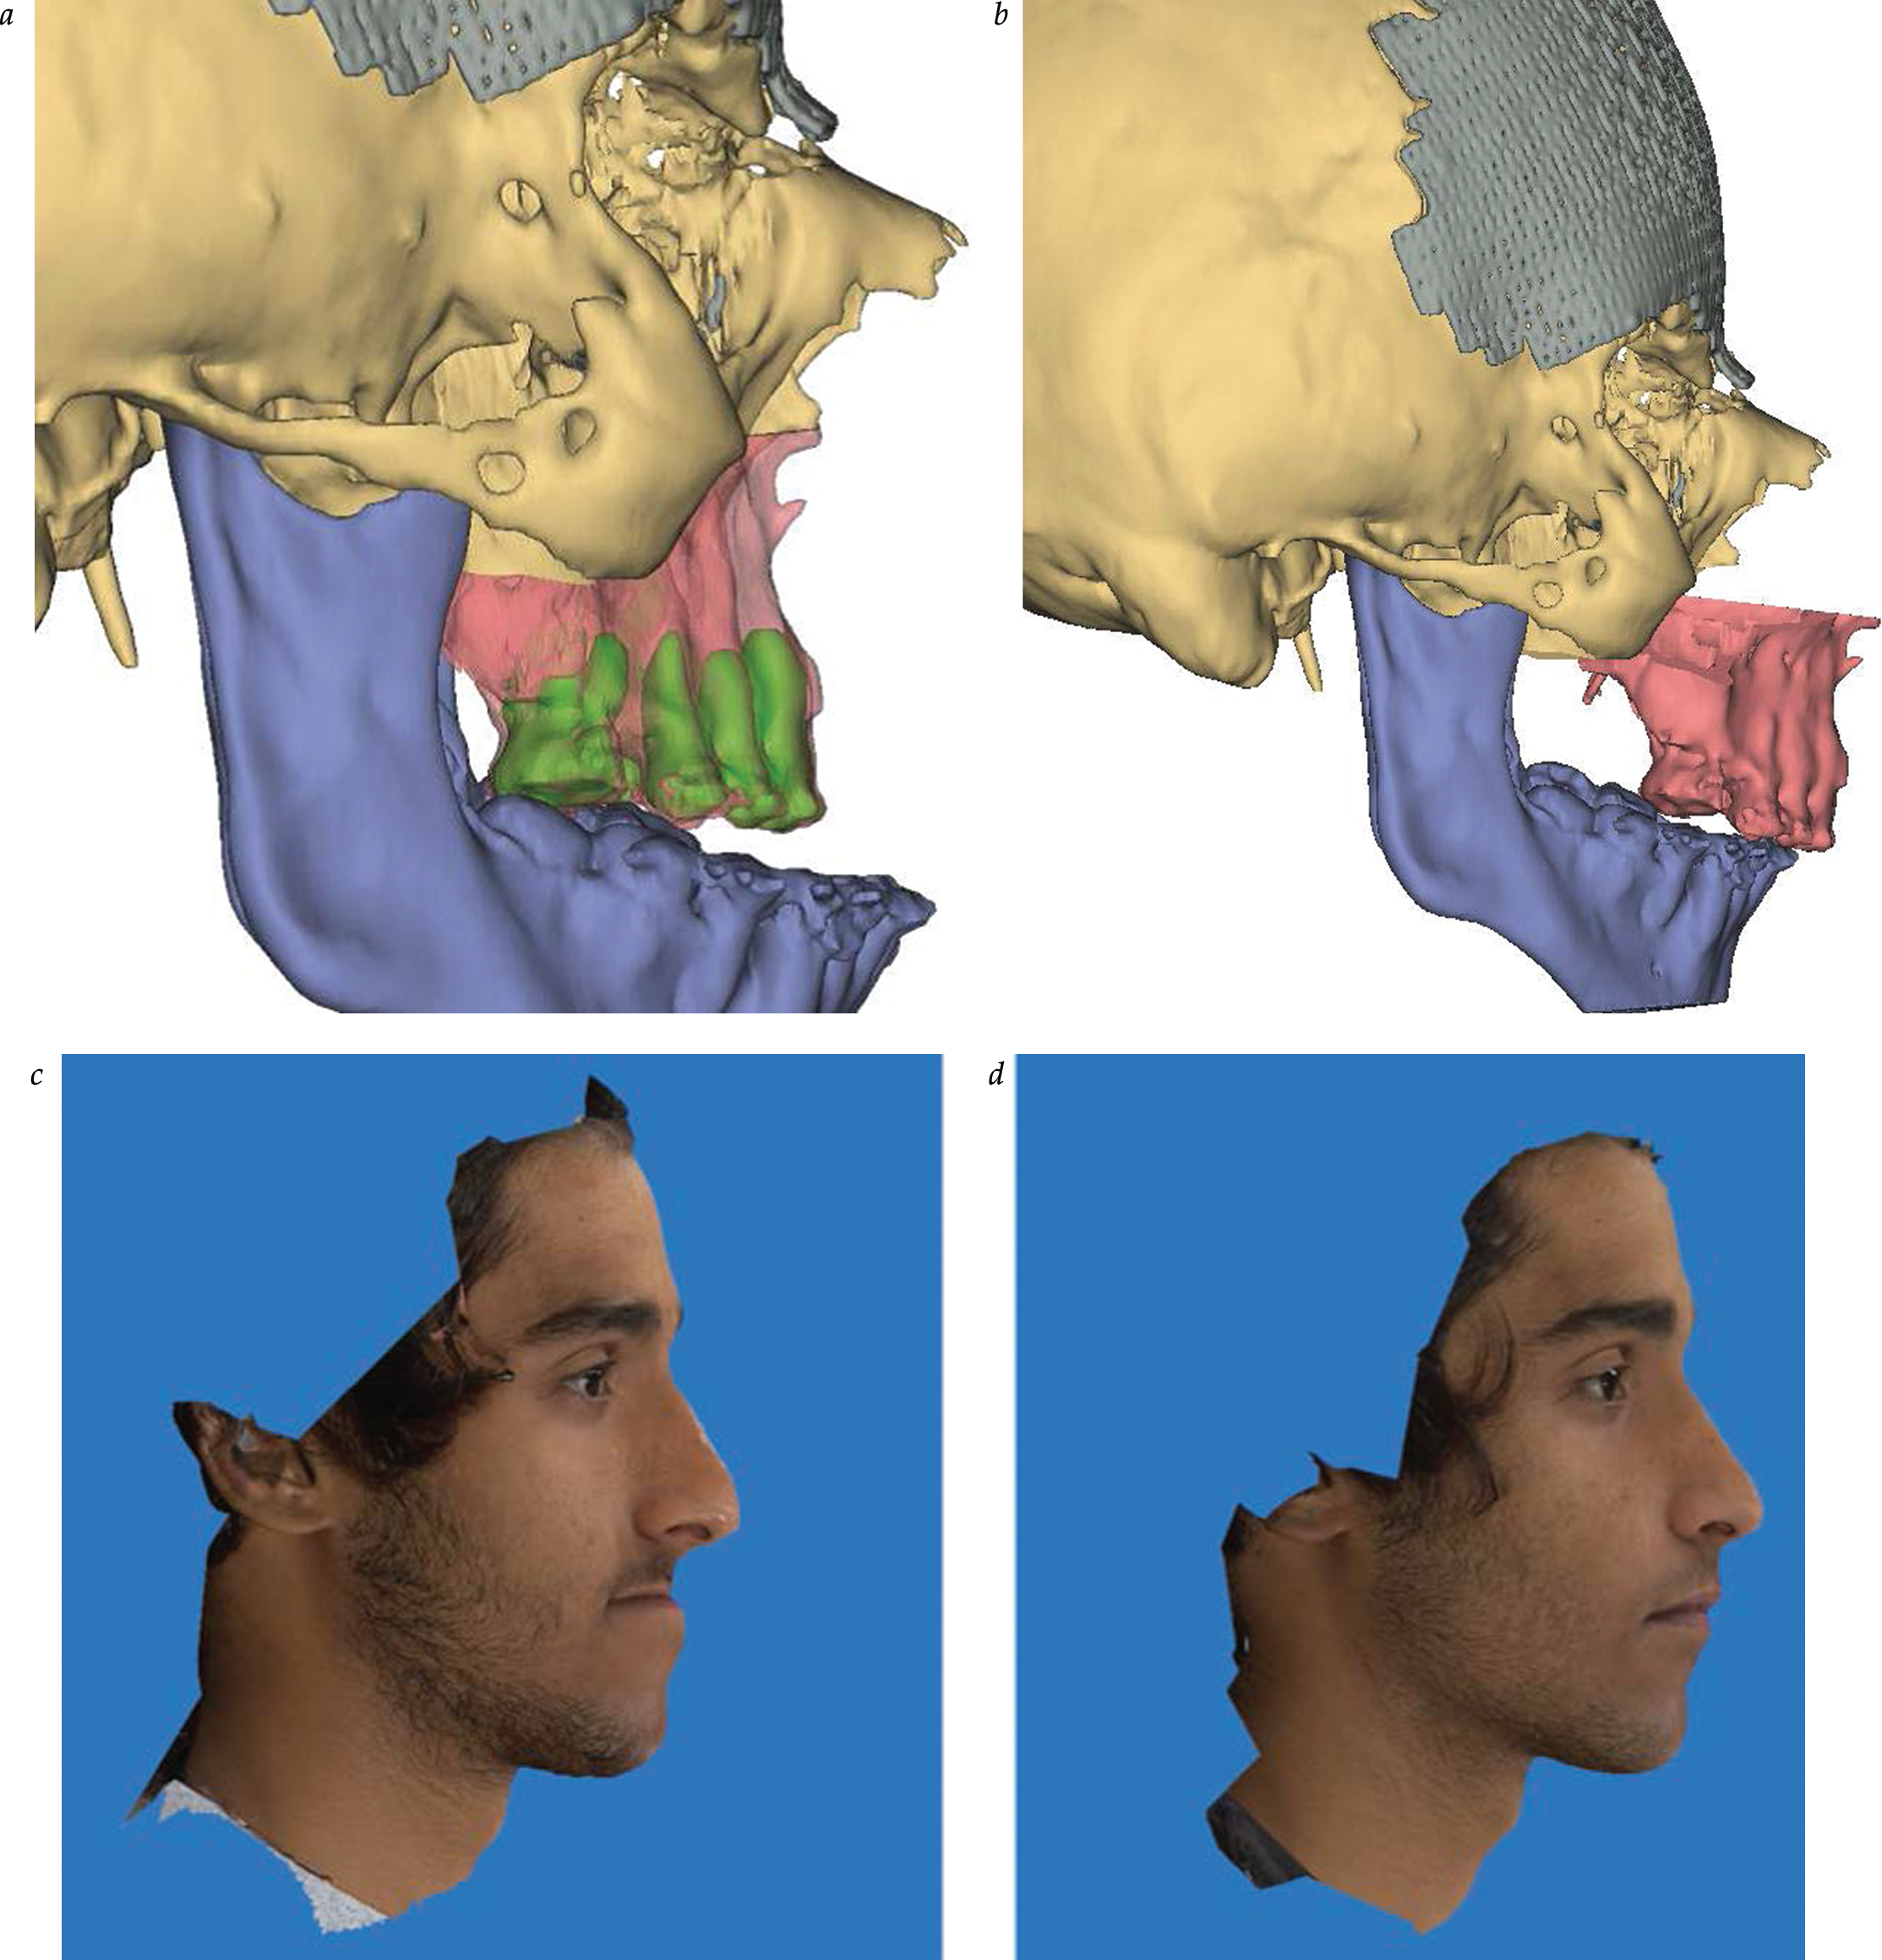

Distraction Osteogenesis in Plastic Surgery

- Distraction osteogenesis offers a unique opportunity to create new bone stock in areas of the craniofacial skeleton where bone is inadequate.

- The osteotomy site, vector, device selection, and timing are all important determinants of success in craniofacial distraction osteogenesis.

- Technological advances in both external and internal distraction devices allow for increased operative flexibility and creativity.

- 3D computer-aided design/manufacturing planning, increased device flexibility, and customized osteotomies allow for further tailoring of distraction osteogenesis to meet individual patient needs.